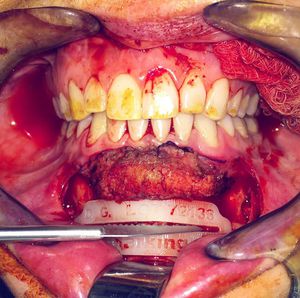

Advancement genioplasty to augment the chin 💀Depicted here is the saw about to make the bony cut on a 3dprinted custom cutting guide, note the exposed mentalis muscle fibers. 🛠💪🙌🔧Some patients have retrogenia or excessively small chins, some have macrogenia, or slightly too large chins, the bone can be advanced or set back to achieve the ideal contour to optimize !•